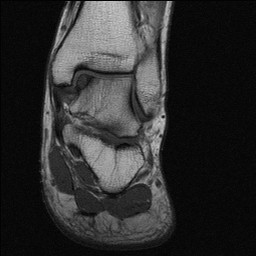

5.氣管支氣管瀰漫性狹窄變形應與感染性肉芽腫病、硬結病、氣管的外壓性狹窄、結節病腫瘤、慢性阻塞性肺疾病的劍鞘樣支氣管病、澱粉樣變、先天性氣管和支氣管軟化症等疾病鑑別,一般上述疾病經活組織檢查可明確診斷(圖9,10,11,12)。

1.X線檢查:胸片顯示有肺不張及肺炎。氣管支氣管體層攝影可見氣管、支氣管普遍性狹窄,尤其兩臂後伸挺胸側位相可顯示氣管局限塌陷。同時也能顯示主動脈弓進行性擴大,升和降主動脈耳廓、鼻、氣管和喉有鈣化。周圍關節的X線顯示關節旁的骨密度降低,偶有關節腔逐漸狹窄但沒有侵蝕性破壞。脊柱一般正常,少數報告有嚴重的脊柱後凸、關節腔狹窄、腰椎和椎間盤有侵蝕及融合改變。恥骨和骶髂關節有部分閉塞及不規則的侵蝕。

2.CT可發現氣管和支氣管樹的狹窄程度及範圍,可發現氣管和支氣管 壁的增厚鈣化、管腔狹窄變形及腫大的縱隔淋巴結。呼氣末CT掃描可觀察氣道的塌陷程度高分辨CT可顯示亞段支氣管和肺小葉的炎症。氣道的三維重建可提示更多的信息。